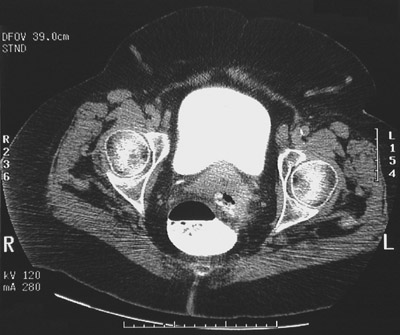

| In this pelvic CT scan is an area of abscess formation containing contrast and air. The abscess is located posterior to the uterus and anterior to the bright contrast-filled sigmoid colon. This abscess resulted from a ruptured diverticulum. The patient should have ingested more dietary fiber to help prevent diverticulosis and its complications. |